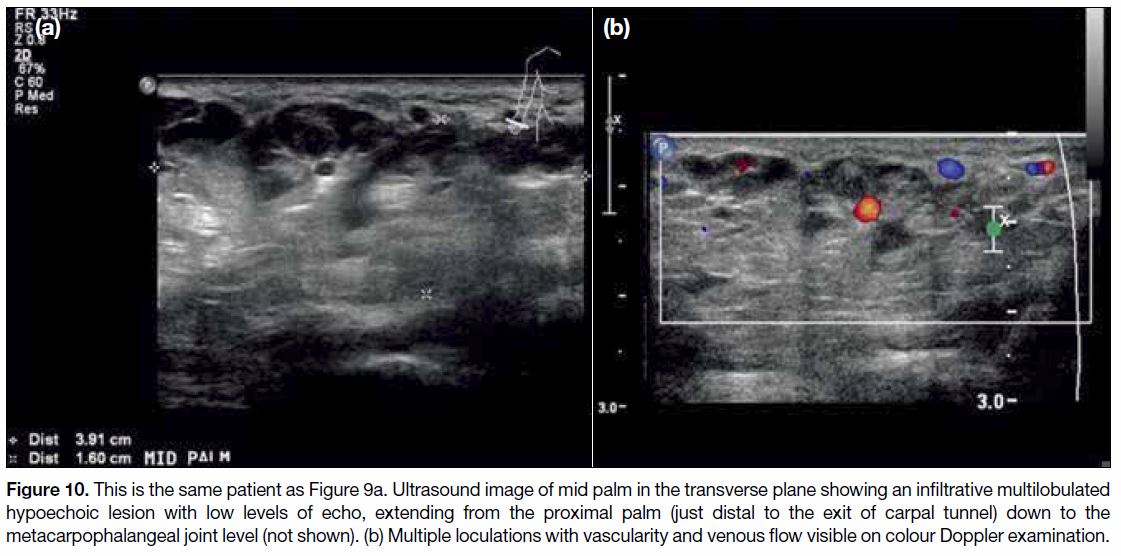

Venous Malformation

Vascular malformations can be subcategorized according

to their flow dynamics into low and high flow types.[20]

Low flow types include venous, lymphatic, capillary-venous and capillary-lymphatic-venous malformations.

The presence of an arterial component indicates a high

flow lesion that includes arteriovenous malformations and arteriovenous fistulas. Venous malformation

(Figures 9 and 10) is the most common peripheral

vascular malformation, usually seen in the head and neck

region, trunk and extremities. Venous malformation

typically presents as a soft, compressible and non-pulsatile

slow-growing mass. On MRI (Figure 11),

vascular malformations are seen as infiltrative lobulated

lesions without significant mass effect, with hyperintense

T2 signal and gradual enhancement on post-contrast

images. Phleboliths may be present. No flow void is

demonstrated. Delayed contrast-enhanced sequences are

also helpful in demonstrating any connection between

the malformations and deeper venous vessels. This is

an important detail to confirm prior to intervention since

these lesions have been linked to a greater risk of deep

venous thrombosis.[21]

Figure 10. This is the same patient as Figure 9a. Ultrasound image of mid palm in the transverse plane showing an infiltrative multilobulated

hypoechoic lesion with low levels of echo, extending from the proximal palm (just distal to the exit of carpal tunnel) down to the

metacarpophalangeal joint level (not shown). (b) Multiple loculations with vascularity and venous flow visible on colour Doppler examination.